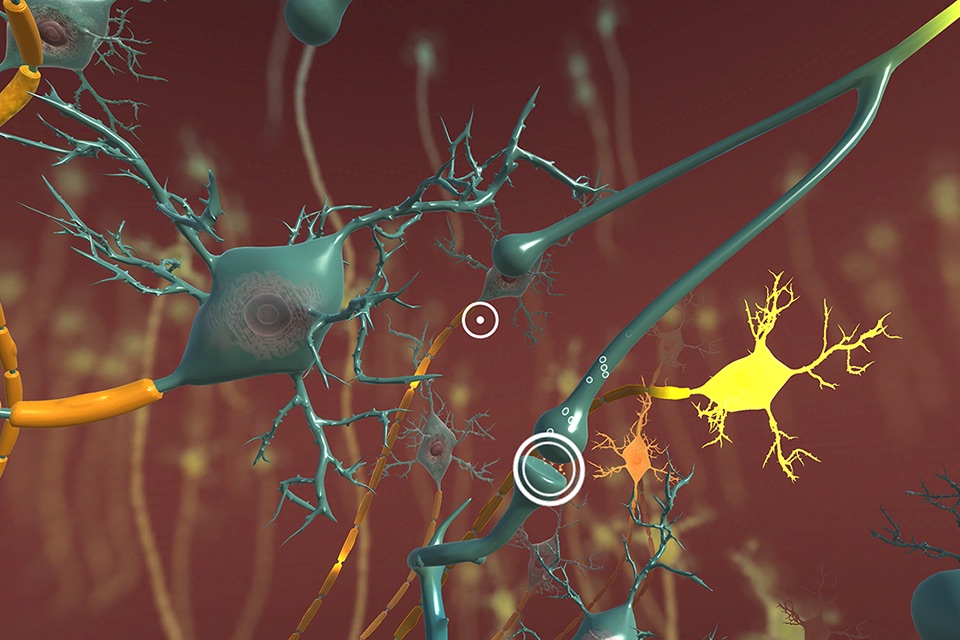

The INVIVO Bloodstream and CNS Explorer is a virtual reality experience designed for Touchscreens and Google Cardboard.

The combination of INVIVO’s world-class 3D content and technical expertise has created a virtual environment like no other. An immersive educational experience, Bloodstream and CNS Explorer transports you to the interior of a blood vessel or into the CNS to learn about human anatomy from an impossible viewpoint.